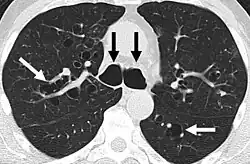

- Síndrome de Mounier-Kuhn o traqueobroncomegalia: caracterizado por un marcado aumento del calibre de la tráquea y los bronquios principales.[4]

- Bronquiectasias quísticas: dilataciones saculares de los bronquios que aparecen en enfermedades como la fibrosis quística o la discinesia ciliar primaria.